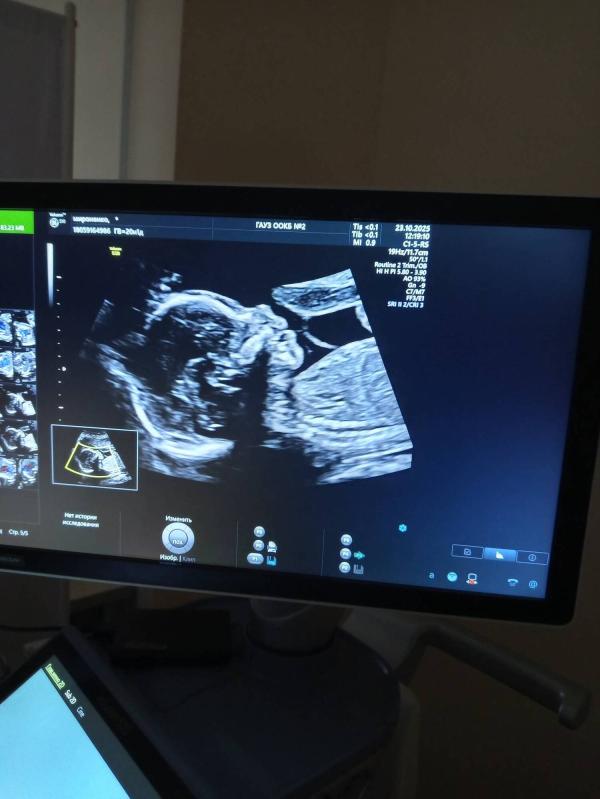

Как свыкнуться с тем , что у меня там 2 человека 🤷 да, двойня, да, мальчик и девочка... Но полного осознания нет , наверное, поверю, только после их рождения 😅

1 - девочка🩷 2 - мальчик💙

На первом , на втором просто все подтвердили)